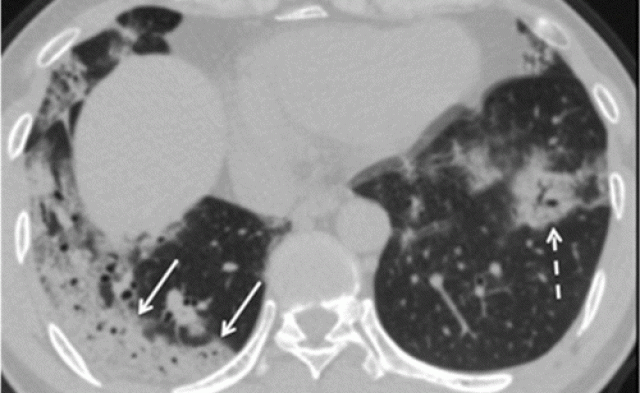

Si se pregunta por qué este proyecto de ley milagroso se apresuró al escritorio del presidente Trump , realmente debería echar un buen vistazo a las tomografías computarizadas de pacientes que tienen lesiones pulmonares inducidas por radiación y compararlas con las tomografías computarizadas de pacientes infectados con el coronavirus Enfermedad de COVID-19, que le explicará por qué la Sociedad Radiológica de América del Norte acaba de emitir una alerta de emergencia que declara que las tomografías computarizadas deben usarse como la herramienta de detección primaria para COVID-19 .

Tomografías computarizadas de pacientes con lesión pulmonar inducida por radiación ( arriba ) …

… Coinciden casi exactamente con las tomografías computarizadas tomadas de pacientes infectados con la enfermedad del coronavirus COVID-19 ( arriba )